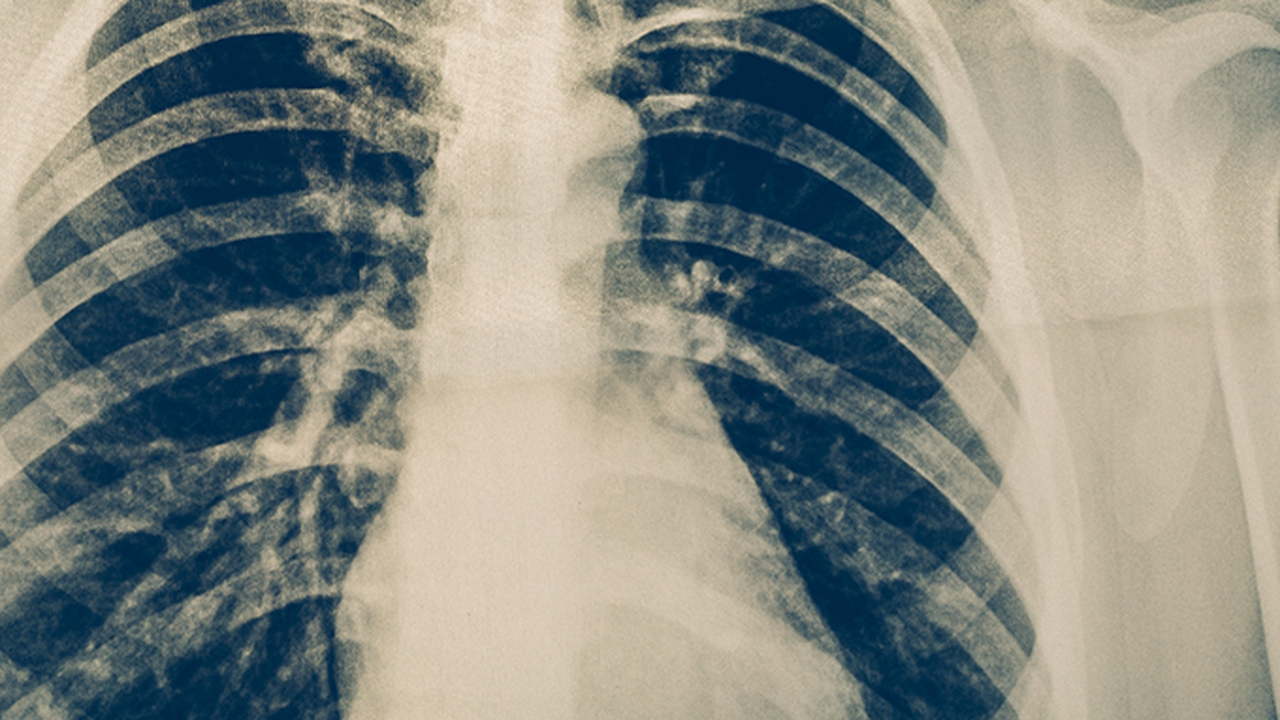

肺癌是一种常见的恶性肿瘤,其发病原因复杂,包括吸烟、空气污染、职业暴露等多种因素。早期诊断和治疗对提高患者生存率至关重要。